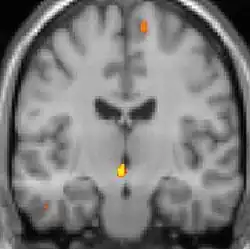

| Positron emission tomography (PET) shows brain areas being activated during pain. | ||

Positron emission tomography (PET) scans indicate the brain areas which are activated during attack only, compared to pain free periods. These pictures show brain areas that are active during pain in yellow/orange color (called "pain matrix"). The area in the center (in all three views) is activated only during cluster headaches. The bottom row voxel-based morphometry shows structural brain differences between individuals with and without CH; only a portion of the hypothalamus is different.[36]